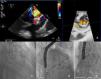

Surgical replacement of the mitral valve with a biologic prosthesis (31 mm Carpentier Edwards) was performed. Four months later, he was admitted for symptomatic hemolytic anemia (hemoglobin 9 g/dl, high lactate dehydrogenase and undetectable haptoglobin). Transesophageal echocardiography (TEE) showed severe antero-lateral paraprosthetic regurgitation (Figure 1A and B). Reoperation was proposed and refused by the patient. For this reason, and also because of his high surgical risk, it was decided to perform percutaneous paravalvular leak (PVL) closure.

The procedure was performed under general anesthesia, via the left femoral vein under fluoroscopic and TEE guidance. After transseptal puncture, a NuMED Tyshak II 12 mm×40 mm balloon was inflated at low pressure until complete closure was achieved and used to assess the dimension of the leak and choose the appropriate device. Two 7F sheaths (AGA Medical Corporation) were advanced across the mitral leak and an Amplatzer Vascular Plug III was deployed (Figure 1C) but still attached to the delivery cable. As the second sheath was occlusive (Figure 1D), it was decided to place a round device, an 8/6 mm Amplatzer Duct Occluder (Figure 1E). Only residual paraprosthetic regurgitant flow persisted and both devices were released. There was significant clinical improvement.

TEE revealed severe paraprosthetic regurgitation in an anterior position, close to the previously implanted devices (Figure 2B). Only one of the two devices was identified. Fluoroscopy confirmed embolization of the Amplatzer Duct Occluder to the left femoral artery (Figure 2A). Percutaneous removal was attempted but was unsuccessful and surgical removal was performed.

Fluoroscopy showing embolization of the Amplatzer Duct Occluder to the left femoral artery (A). Transesophageal echocardiography (TEE) revealed severe paraprosthetic regurgitation (B). An Amplatzer Muscular VSD Occluder was implanted near to the previous device (C). Three months later, TEE showed moderate paraprosthetic regurgitation (D). The devices were surgically removed (E).